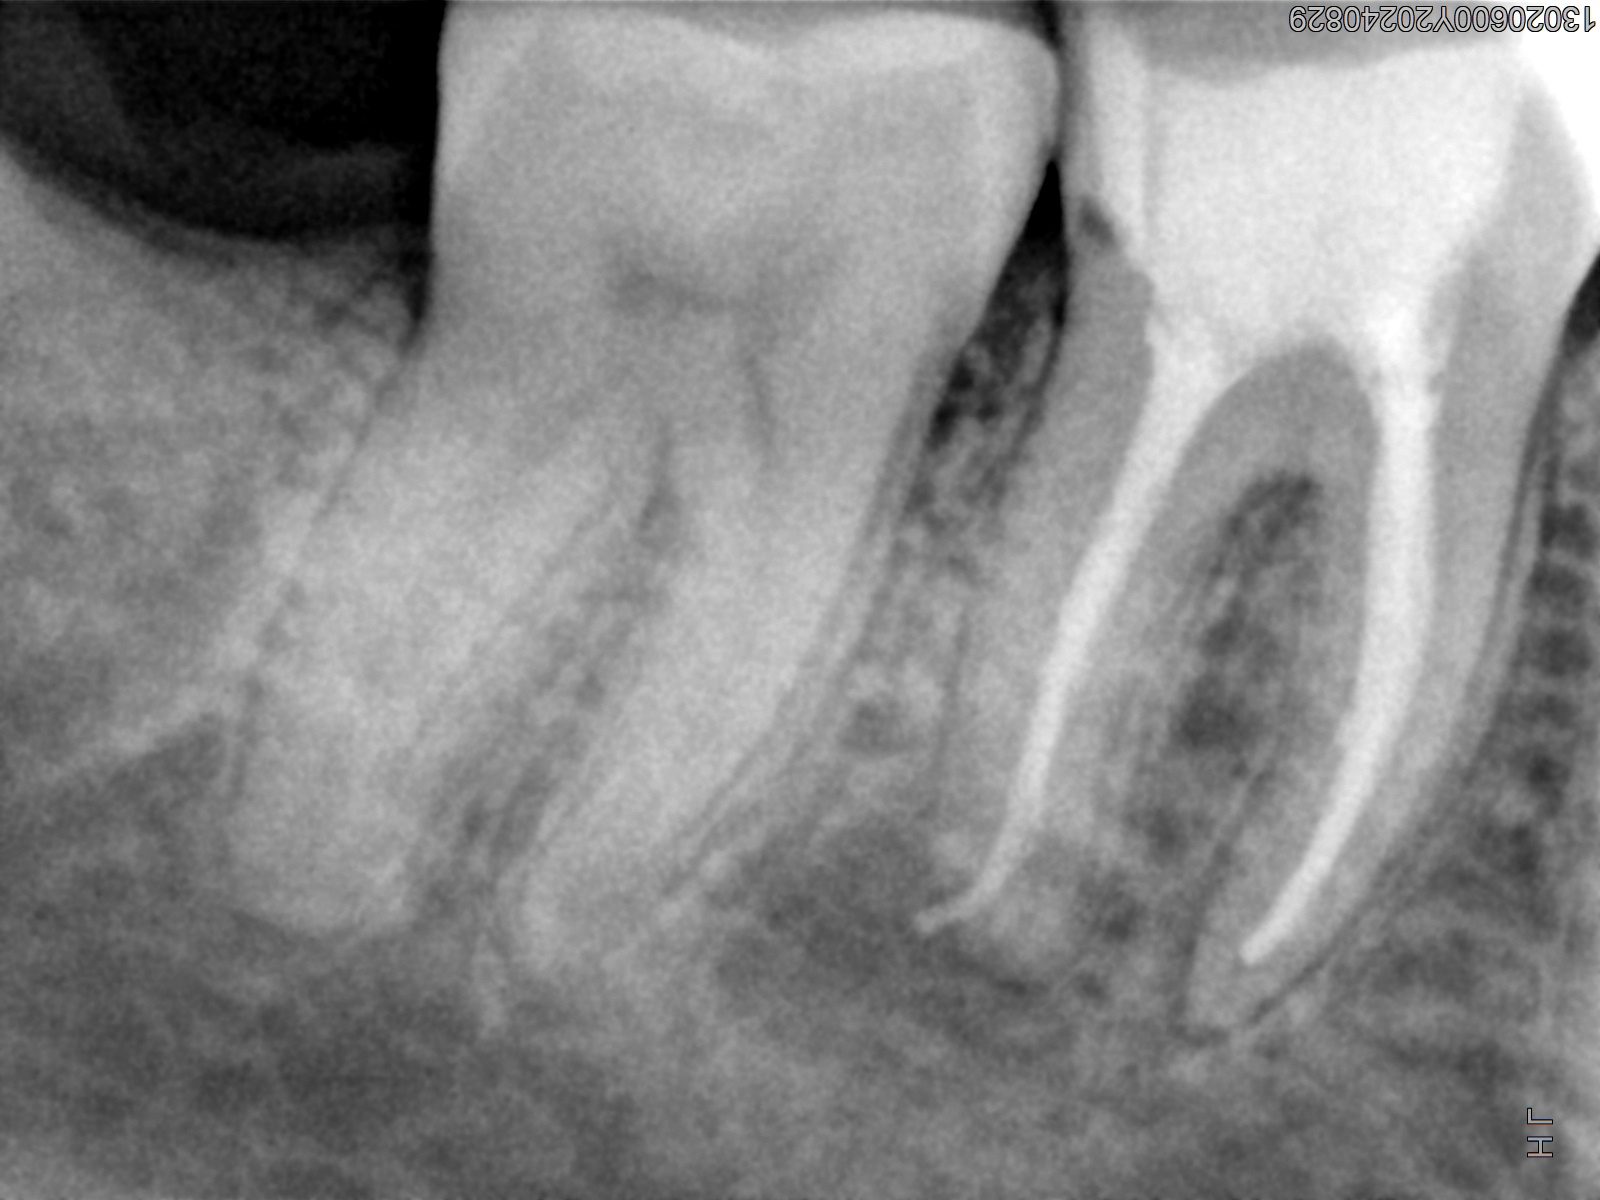

Veja alguns casos de sucesso